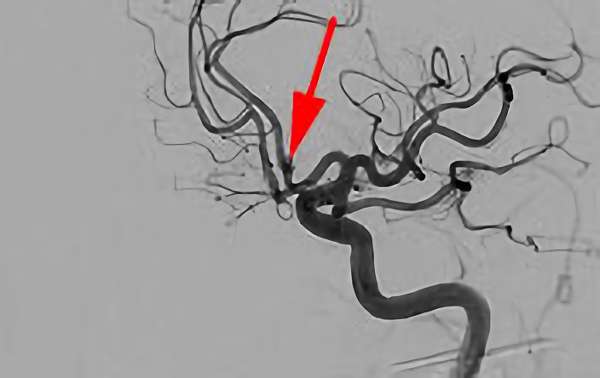

前交通動脈瘤

No.1627 手術前